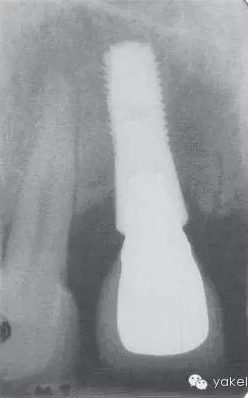

LR5種植修復(fù),種植體-基臺(tái)連接處有殘余粘結(jié)劑未被清除,最終導(dǎo)致種植體周圍炎(圖3)。

圖.3 影像學(xué)顯示下頜前磨牙種植體。冠沒有完全就位,可見過量的殘余粘結(jié)劑,最終導(dǎo)致種植體周圍炎。